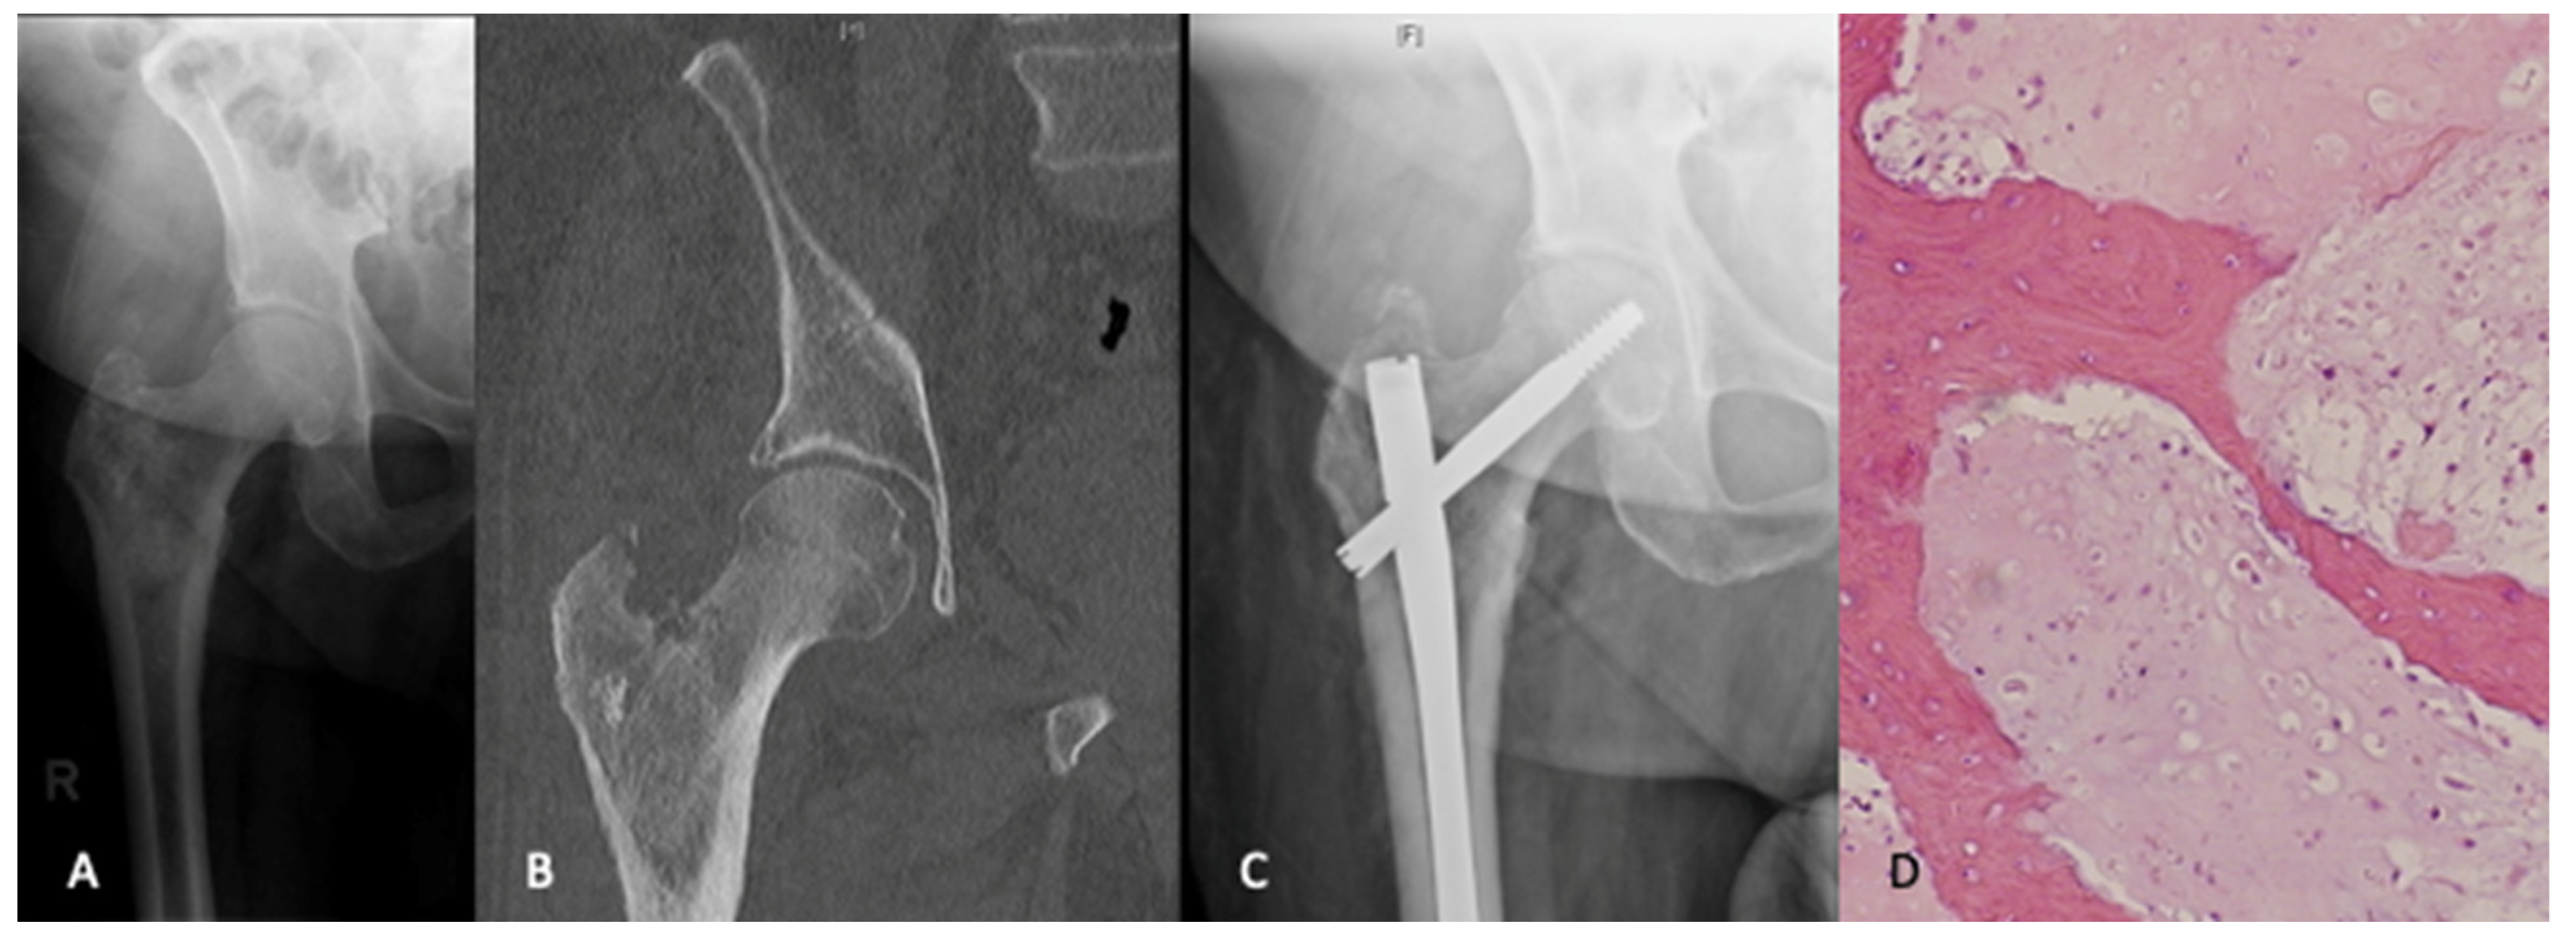

The “whoops” operation, management of a primary bone tumour with intramedullary nail fixation, is a disastrous event [15]. Intramedullary fixation contaminates the entire canal with tumour, as well as seeds the proximal and distal locking screw tracts, and the entry points for the nail in the proximal femur. The limb is often not salvageable, and a hip disarticulation may be required for local disease control (Figure 1). Patients with primary bone tumors who undergo inappropriate initial surgical management have higher rates of local recurrence and mortality, lower rates of limb salvage and worse functional outcomes [15,16,17].

Figure 1.

An 80-year-old male presented with ongoing right hip pain and lesion in the peritrochanteric region that was thought to be metastatic disease (A,B). A workup for an unknown primary lesion was negative. The patient underwent intramedullary nail fixation for impending pathologic fracture (C). The pathologic findings from intraoperative reamings were consistant with a diagnosis of chondrosarcoma (H&E, ×200). (D). Given the patients age and health status along with the morbidity of a curative procedure, the decision was made to pursue palliative care.